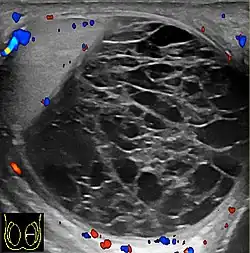

-

Doppler ultrasound of epididymitis, seen as a substantial increase in blood flow in the left epididymis (top image), while it is normal in the right (bottom image). The thickness of the epididymis (between yellow crosses) is only slightly increased (7 mm). -

Doppler ultrasound of the scrotum of the same case, in the axial plane, showing orchitis (as part of epididymo-orchitis) as hypoechogenic and slightly heterogenic left testicular tissue (right in image), with an increased blood flow. There is also swelling of peritesticular tissue.